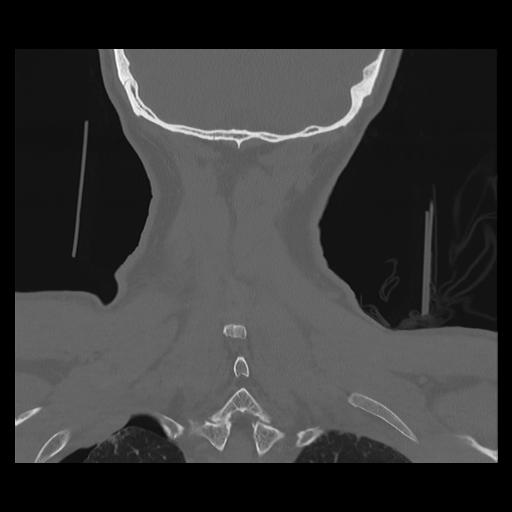

16 HUESO,,Coronal,2.000,HUESO,Coronal,